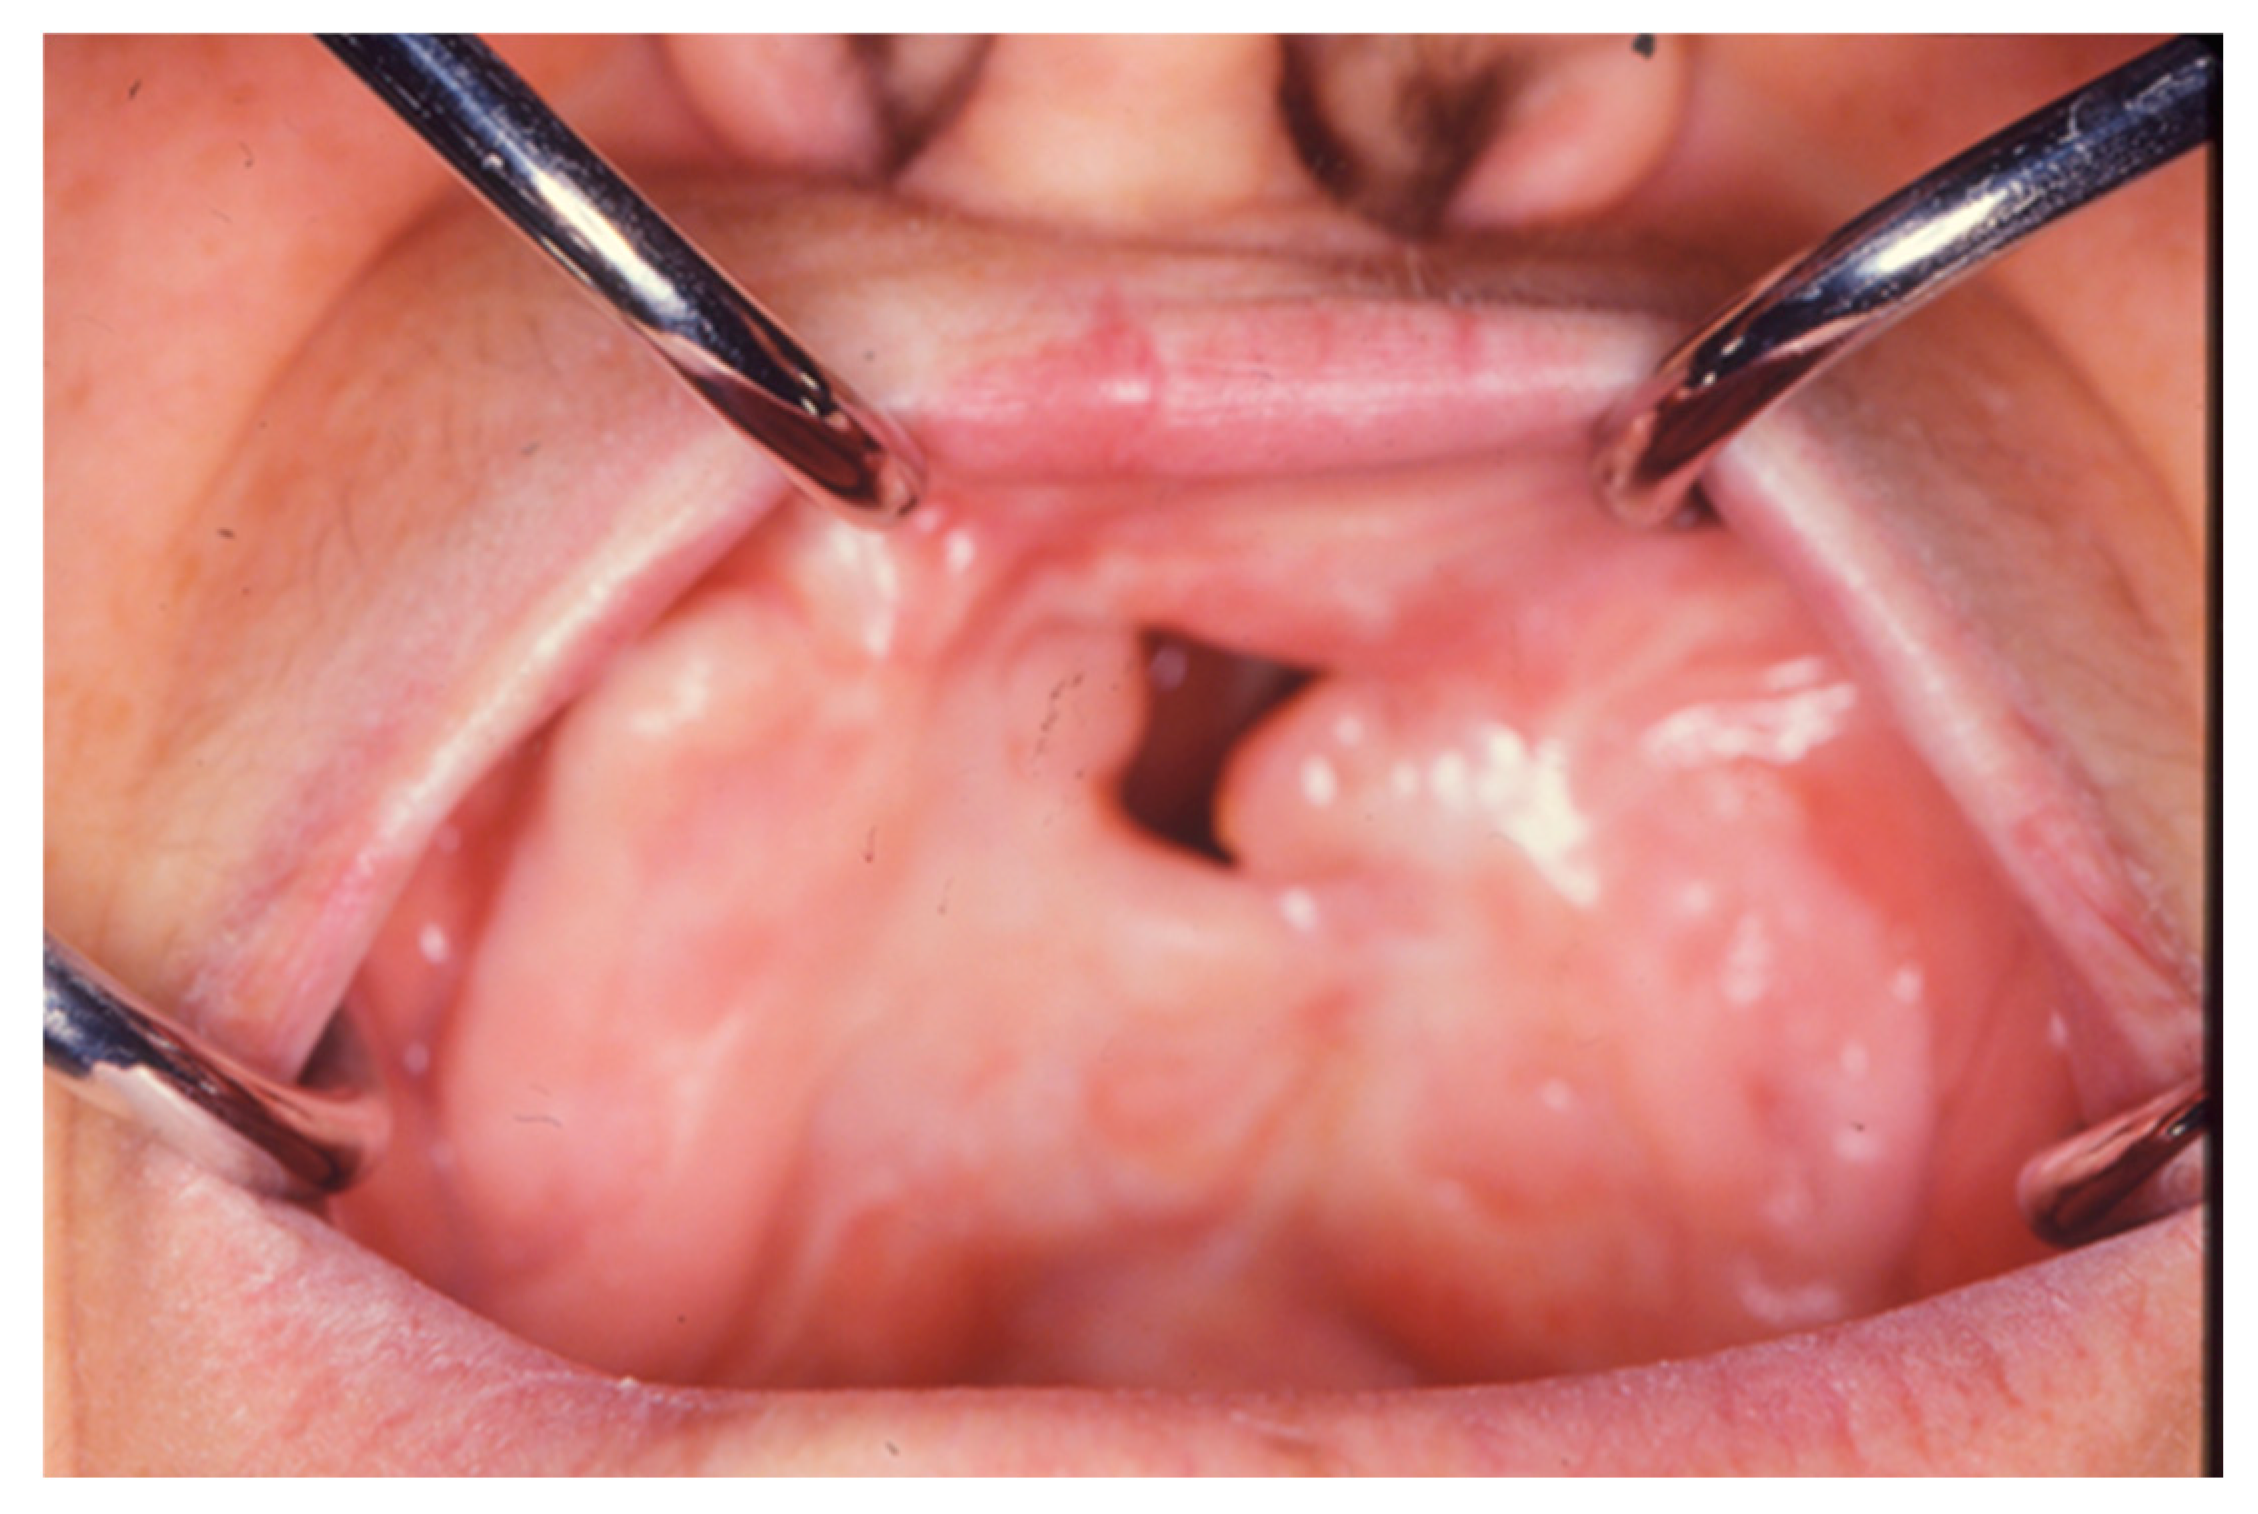

The aim of the study was to provide a summary review of the literature on the surgical techniques currently in use for the resolution of oro-antral communications, that are the trapezoidal, rotated vestibular, rotated palatine, buccal fat pad and double-layered flap techniques; then to describe the central theme of the study, that is the technique of mucogingival plastic surgery with the use of a dorsum of tongue flap (Figure 1) if it is not possible to use adjacent tissue to close the communication.

Figure 1.

In this case we decided to use the technique of mucogingival plastic surgery with the use of a dorsum of tongue flap because it wasn’t possible to use adjacent tissue to close the communication.

In fact, when the tissues adjacent to the oro-antral or oro-nasal communication are unsuitable for the closure of a large sized fistula, a muscolar-mucosal flap from the tongue dorsum can be used and rotated upwards.